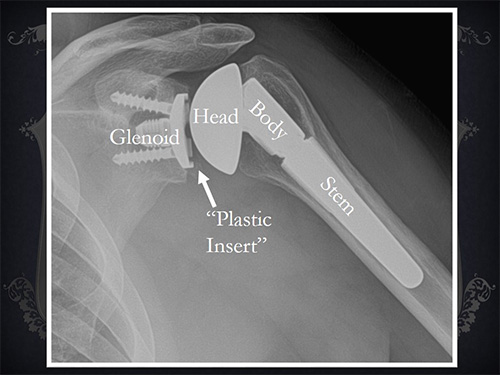

Shree Datta Hospital comprises of a multidisciplinary team that offers a holistic approach in the management of Spinal problems. We aim to provide safe, high quality, cost-effective and state of art, operative and non-operative management of spinal disorders. Multidisciplinary consultation ensures that every patient receives a complete assessment and even the most complex spinal problems will be effectively handled.

ADVANCED SPINE PROCEDURES

Deformity correction is the surgical adjustment or modification of bone that grows incorrectly as the result of a disease or condition.